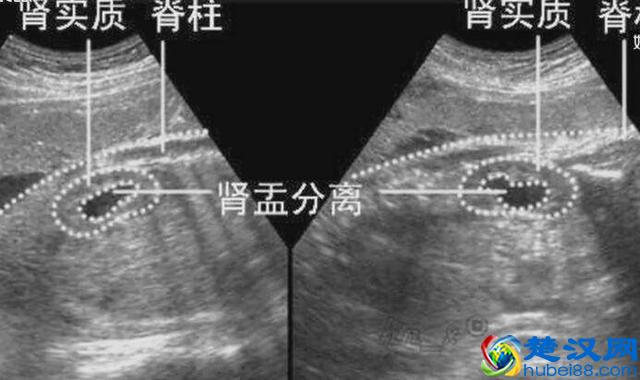

四、肾脏

那么除了颅内和心脏的结构意外,我们还要关注的就是,胎儿腹腔内脏器官是否存在异常。

这其中比较容易出现问题的,就是胎儿的双侧的肾脏,有的时候,我们可以看到彩超单上报的,胎儿的“双侧肾盂增宽”,当然这个增宽到一定程度的话,我们还是要小心,它后续是否会发生肾积水,或者是肾脏其他疾病